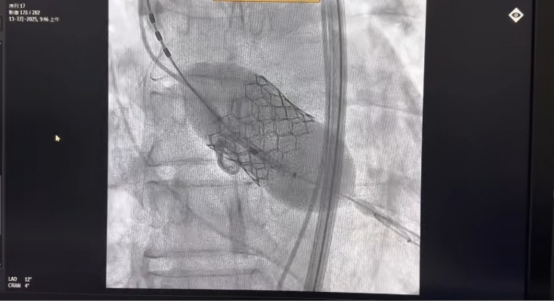

2025年7月13日,我院郭應(yīng)強(qiáng)教授為一名主動(dòng)脈瓣重度狹窄伴反流患者成功實(shí)施機(jī)器人輔助球擴(kuò)式TAVR(Transcatheter Aortic Valve Replacement,經(jīng)導(dǎo)管主動(dòng)脈瓣置換)手術(shù)。術(shù)后患者即刻蘇醒、恢復(fù)良好。這是郭應(yīng)強(qiáng)教授團(tuán)隊(duì)開展的全國首例介入機(jī)器人+TAVR(S3)的臨床試驗(yàn),有望為心臟瓣膜病患者帶來新的手術(shù)方式選擇。該機(jī)器人系統(tǒng)由郭應(yīng)強(qiáng)教授和上海術(shù)濟(jì)客醫(yī)療科技有限公司共同研發(fā),這也標(biāo)志著我院在心臟瓣膜疾病領(lǐng)域再次邁出了精準(zhǔn)化、智慧化的重要一步。

該患者為60歲男性,5+月前無明顯誘因出現(xiàn)心悸。完善超聲心動(dòng)圖提示主動(dòng)脈瓣狹窄(重度)伴反流(中度),二尖瓣狹窄(輕度)伴反流(輕-中度)。術(shù)中,郭應(yīng)強(qiáng)教授在與手術(shù)室相鄰的控制室操作控制臺上的按鍵和手柄,遙控機(jī)器人平臺上的瓣膜器械完成手術(shù)操作。

T AVR手術(shù)在機(jī)器人輔助下,旨在通過高精度、可重復(fù)的操作提升手術(shù)安全性和療效,其核心是通過機(jī)器人系統(tǒng)輔助完成導(dǎo)管操作、瓣膜定位及釋放等關(guān)鍵步驟。該系統(tǒng)采用模塊化設(shè)計(jì),支持亞毫米級精準(zhǔn)操作,并配備力傳感反饋機(jī)制,可實(shí)時(shí)感知導(dǎo)管受力情況,優(yōu)化復(fù)雜血管路徑的導(dǎo)航能力。

與傳統(tǒng)的TAVR手術(shù)相比,其優(yōu)勢在于:一是精準(zhǔn)度與穩(wěn)定性提升,機(jī)器人系統(tǒng)通過機(jī)械臂的穩(wěn)定性和高分辨率影像導(dǎo)航(如CT、超聲實(shí)時(shí)成像),顯著減少人為手顫或操作偏差,提高瓣膜釋放的準(zhǔn)確性,減少對傳導(dǎo)系統(tǒng)的損傷。二是降低并發(fā)癥風(fēng)險(xiǎn),血管并發(fā)癥減少:機(jī)器人輔助系統(tǒng)通過更精準(zhǔn)的導(dǎo)管操作,減少血管穿孔或夾層風(fēng)險(xiǎn)。研究顯示,傳統(tǒng)TAVR的血管并發(fā)癥發(fā)生率約為9%,而機(jī)器人輔助組可降至0%。三是縮短學(xué)習(xí)曲線、提升可重復(fù)性:傳統(tǒng)TAVR依賴醫(yī)生經(jīng)驗(yàn),學(xué)習(xí)曲線長;機(jī)器人系統(tǒng)通過標(biāo)準(zhǔn)化操作流程,尤其適合基層醫(yī)院推廣。四是減少醫(yī)生職業(yè)暴露:機(jī)器人主從控制設(shè)計(jì)使醫(yī)生遠(yuǎn)離X射線輻射,尤其適用于需長時(shí)間操作的復(fù)雜病例。